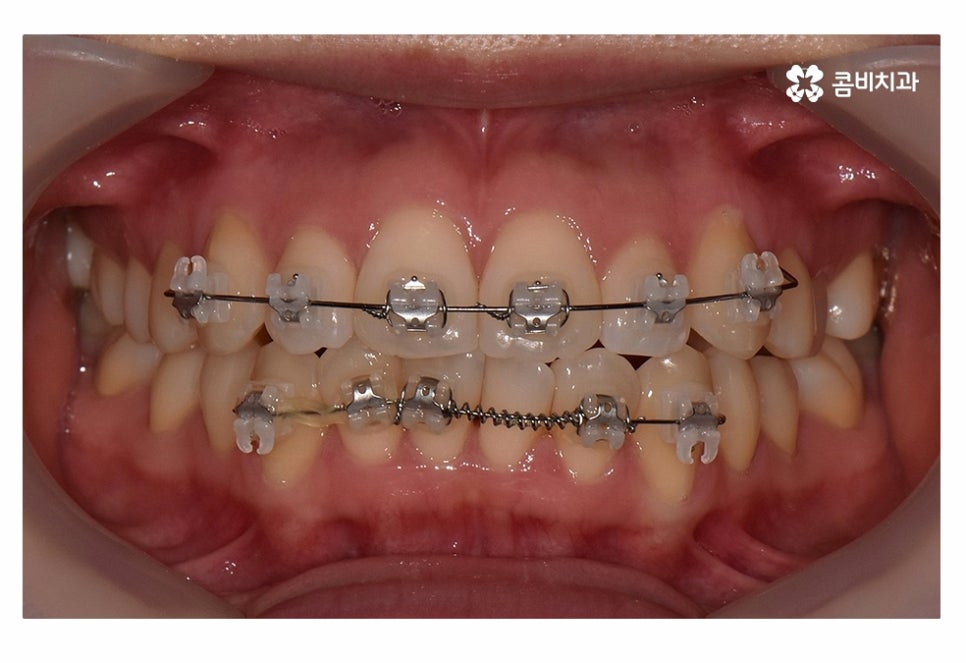

위 사진은 치료가 시작되고 약 5개월 정도가 지난 후의 모습인데

치아부분교정으로도 치열이 빠르게 가지런해진 모습을 볼 수 있어요.